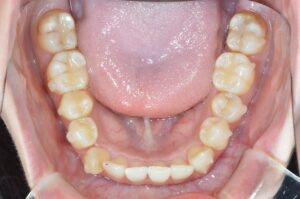

①写真撮影

今の歯並びを色々な角度から撮影します。

せっかくなので矯正前→現在(No.40)で並べてみます。